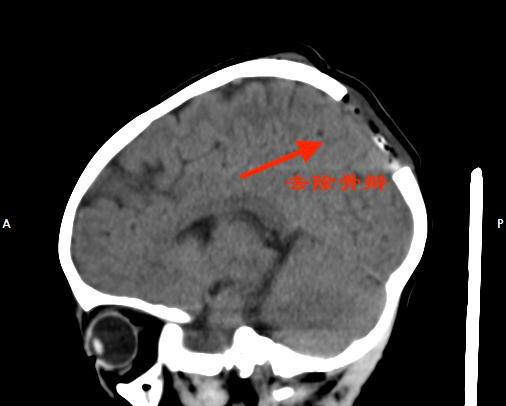

▲术后影像检查

由于目前累及颅骨骨质,采取手术治疗可以达到良好的效果。打开骨窗后,杨宝应在患儿帽状腱膜下发现一个大小约3X3cm²的肿物,部分组织已经破溃并流出脓液。术后病理检查为朗格罕氏细胞组织增生症,嗜酸性肉芽肿。